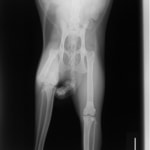

ペルシャ猫 11ヶ月齢 雄

他院にて左大腿骨遠位の成長板骨折(salter-harrisⅠ型)が認められており、治療相談を目的として来院。当院にて、キルシュナーワイヤーを用いたピンニングにより骨折部位の整復を行いました。術後の経過は良好で、現在も経過観察中です。

術前レントゲン